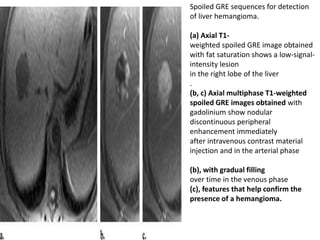

Spoiled GRE sequences for detection

of liver hemangioma.

(a) Axial T1-

weighted spoiled GRE image obtained

with fat saturation shows a low-signal-

intensity lesion

in the right lobe of the liver

.

(b, c) Axial multiphase T1-weighted

spoiled GRE images obtained with

gadolinium show nodular

discontinuous peripheral

enhancement immediately

after intravenous contrast material

injection and in the arterial phase

(b), with gradual filling

over time in the venous phase

(c), features that help confirm the

presence of a hemangioma.